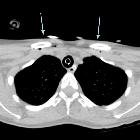

Systemic air

embolism and decompression illnes in a scuba diver.. Gas in retroclavear vessels.

embolism and decompression illnes in a scuba diver.. Arrow shows gas in left innominate vein.